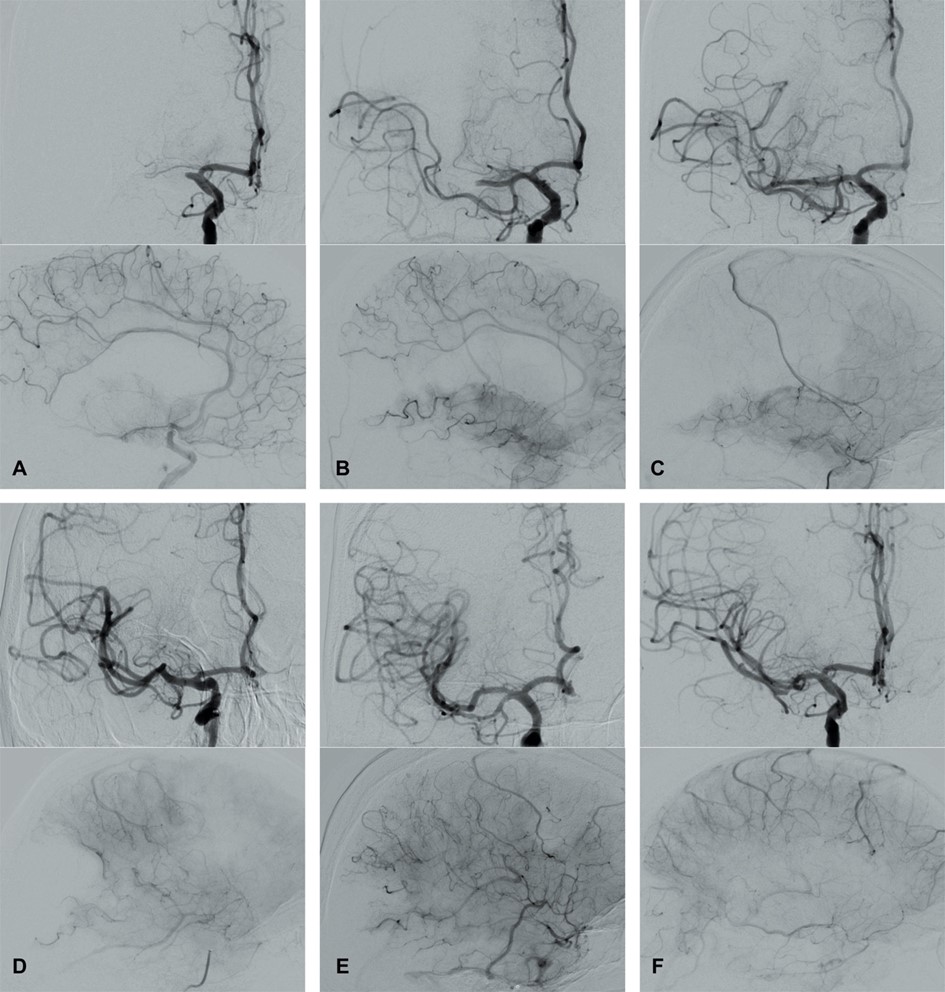

Fig. 4.Modified Thrombolysis in Cerebral Infarction (mTICI) grading system for evaluating the therapeutic success of IVT. No perfusion of the right MCA - mTICI 0 (A). Antegrade reperfusion past the initial occlusion with only filling of a temporal branch of the right MCA - mTICI 1 (B). Antegrade reperfusion of only the superior division of the right MCA - mTICI 2a (C). Antegrade reperfusion of more than half of the previously occluded right MCA territory with persistent filling defect parieto-occipital - mTICI 2b (D). Near complete perfusion except for some distal emboli in several distal cortical vessels frontal and occipital - mTICI 2c (E). Complete antegrade reperfusion of the previously occluded right MCA - mTICI 3 (F).